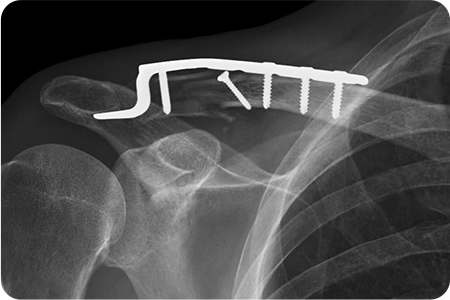

쇄골 골절 수술

쇄골 위쪽을 따라 약 5~8cm 정도 절개하여

골절 부위를 노출합니다. 정복과 고정을 시행하고

절개 부위를 봉합합니다. 수술 후 일정 기간 동안

팔의 움직임을 제한해 뼈가 안정적으로 붙도록 합니다.